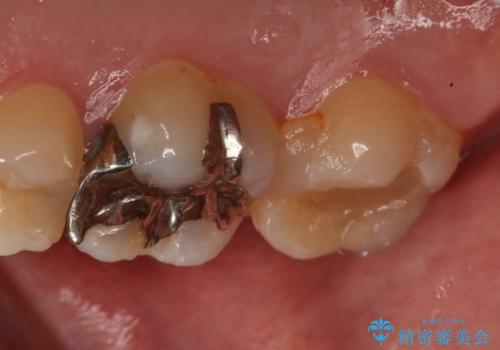

- 右上大臼歯の再治療を希望され来院された患者様です。

切削量と形状を考慮し、インレーでの治療を計画しました。

患者様がゴールドを希望されたのでゴールドインレーを選択しました。

ゴールドは金属の中でも硬すぎず破折すこともほとんどないため歯科の治療に適した材料と言われています。